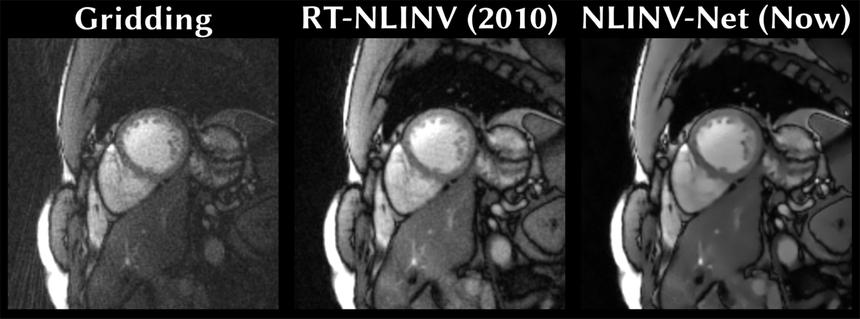

Ученые Технического университета Граца разработали метод, который позволяет получать точные изображения сердцебиения в реальном времени с помощью ограниченного объема данных МРТ. Эта работа, опубликованная в журнале Magnetic Resonance in Medicine, обещает значительно упростить процесс медицинской визуализации.

Используя продвинутые нейронные сети и методы самообучения, международная команда ученых смогла создавать четкие МРТ-изображения даже без идеальных тренировочных данных. Система делит исходные измерения на две части: одна используется для восстановления изображения, а вторая помогает проверять точность реконструкции.

© TU Graz—Institute of Biomedical Imaging